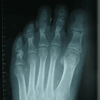

Caso 2: Hallux Valgus del Adolescente

Pie Izquierdo operado